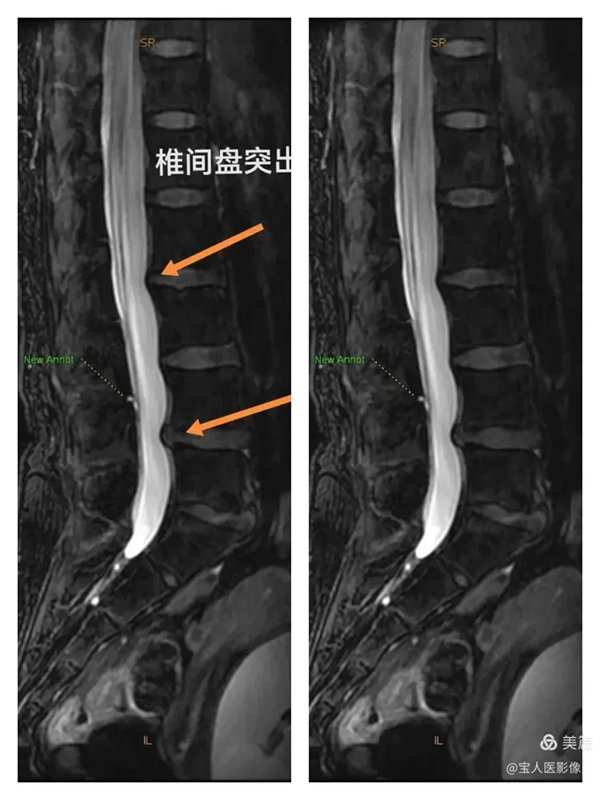

最大密度側面圖,顯示腰段硬膜囊內腦脊液(高信號),前方的椎間盤受壓弧形凹陷,后方的局部膨出。